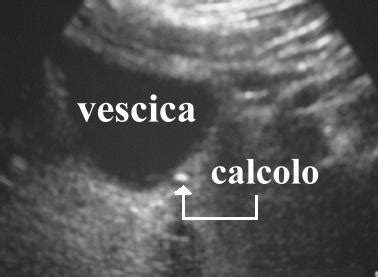

- Formazione di Calcoli Vescicali: La stasi urinaria prolungata può favorire la precipitazione di sali minerali normalmente disciolti nell'urina, portando alla formazione di calcoli nella vescica. Questi calcoli possono causare dolore, infezioni e ulteriore ostruzione.

- Ecografia Prostatica (Sovrapubica e Trans-rettale): L'ecografia è un'indagine di imaging fondamentale. L'ecografia sovrapubica valuta le dimensioni della vescica, lo spessore delle sue pareti (che può aumentare in caso di ostruzione severa a causa dello sforzo del muscolo vescicale) e la presenza di residuo post-minzionale (la quantità di urina che rimane in vescica dopo aver urinato). L'ecografia trans-rettale (TRUS), eseguita con una sonda inserita nel retto, fornisce un'immagine dettagliata della prostata, delle sue dimensioni, della sua struttura e della presenza di eventuali lesioni sospette.